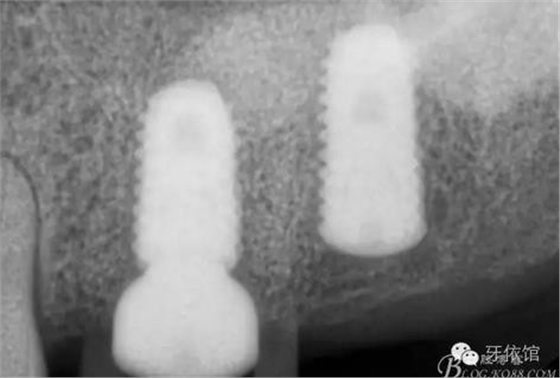

這是術后1月的片子,重新就位愈合基臺

術后6個月口內(nèi)照